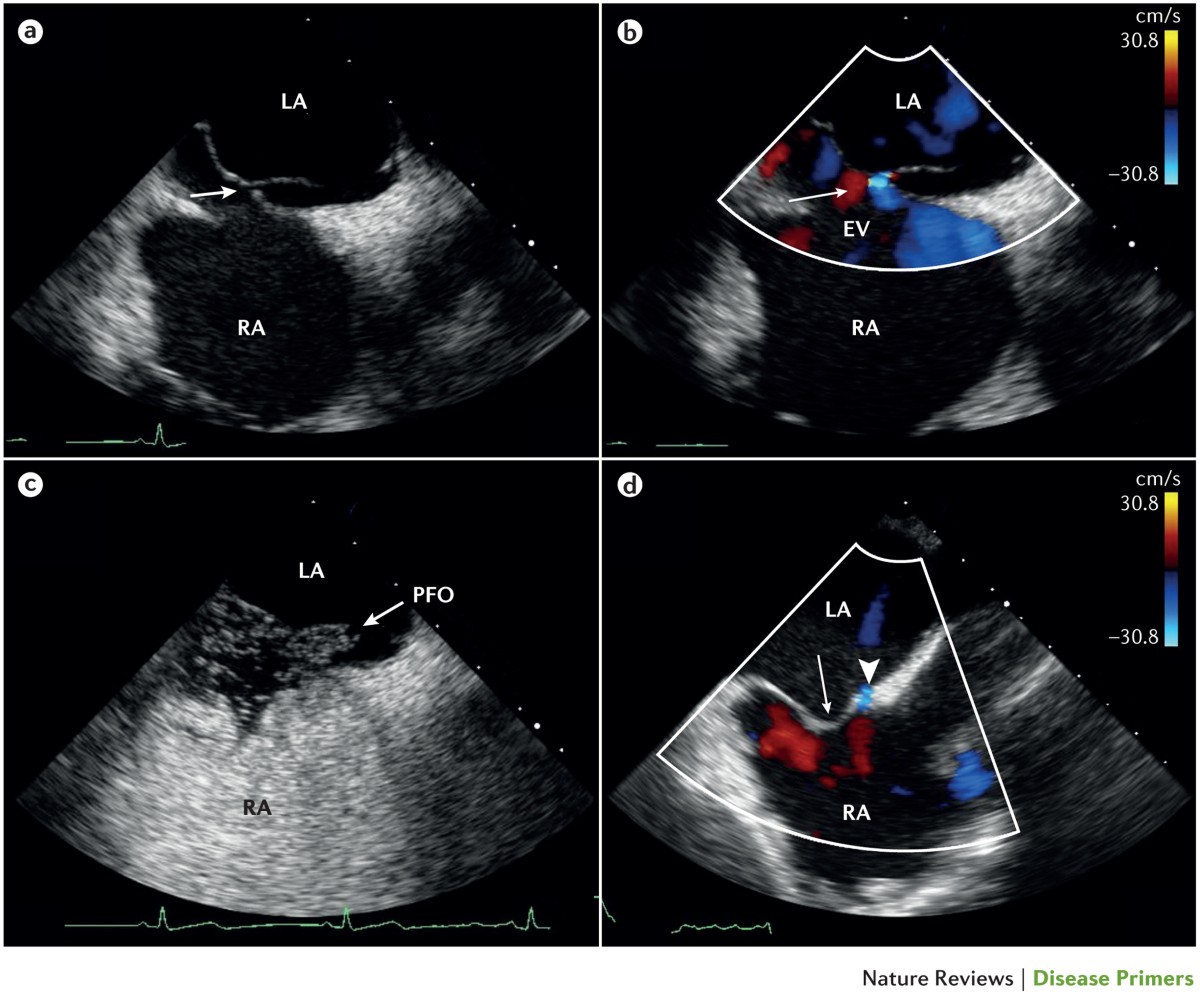

pfo echocardiography sale